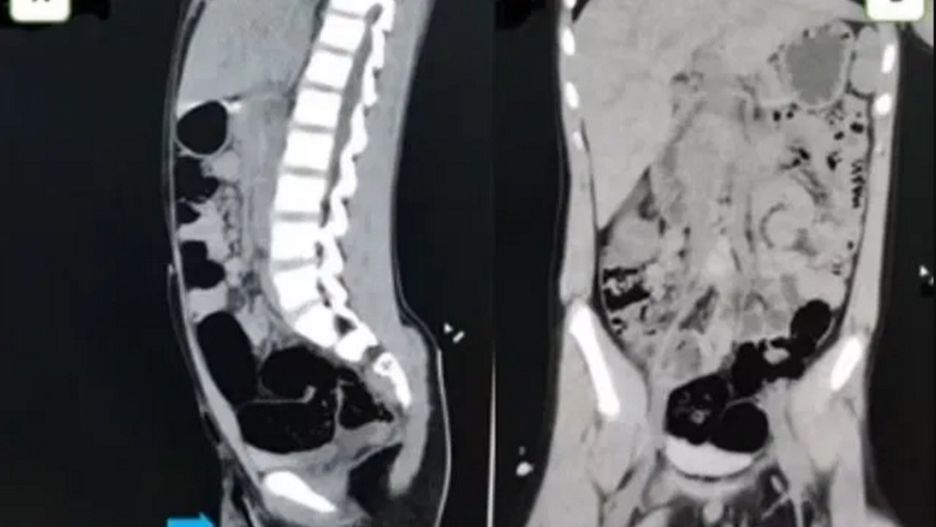

5-centymetrowy patyk (pokazany niebieską strzałką) wbity w mosznę chłopca. 5-centymetrowy patyk (pokazany niebieską strzałką) wbity w mosznę chłopca.

Kiedy chłopiec trafił do szpitala lekarze delikatnie wyjęli z jego ciała 5-centymetrowy patyk i podali mu antybiotyki. Medycy w rozmowie z Daily Mail przekazali, że chłopiec miał "szczęście", że kij nie uszkodził jąder ani tętnic, co mogło doprowadzić do poważnych obrażeń.

Przerażające zdjęcia rentgenowskie pokazały, że gałąź przebiła lewą dolną część moszny i dotarła aż do kości łonowej. Chłopiec otrzymał także szczepionkę przeciw tężcowi, aby powstrzymać rozwój infekcji.